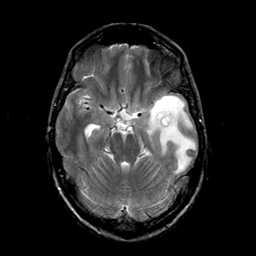

Metastatic bronchogenic carcinoma: T2-weighted MR -- Slice #7

[Home][Help][Clinical] Slice 7